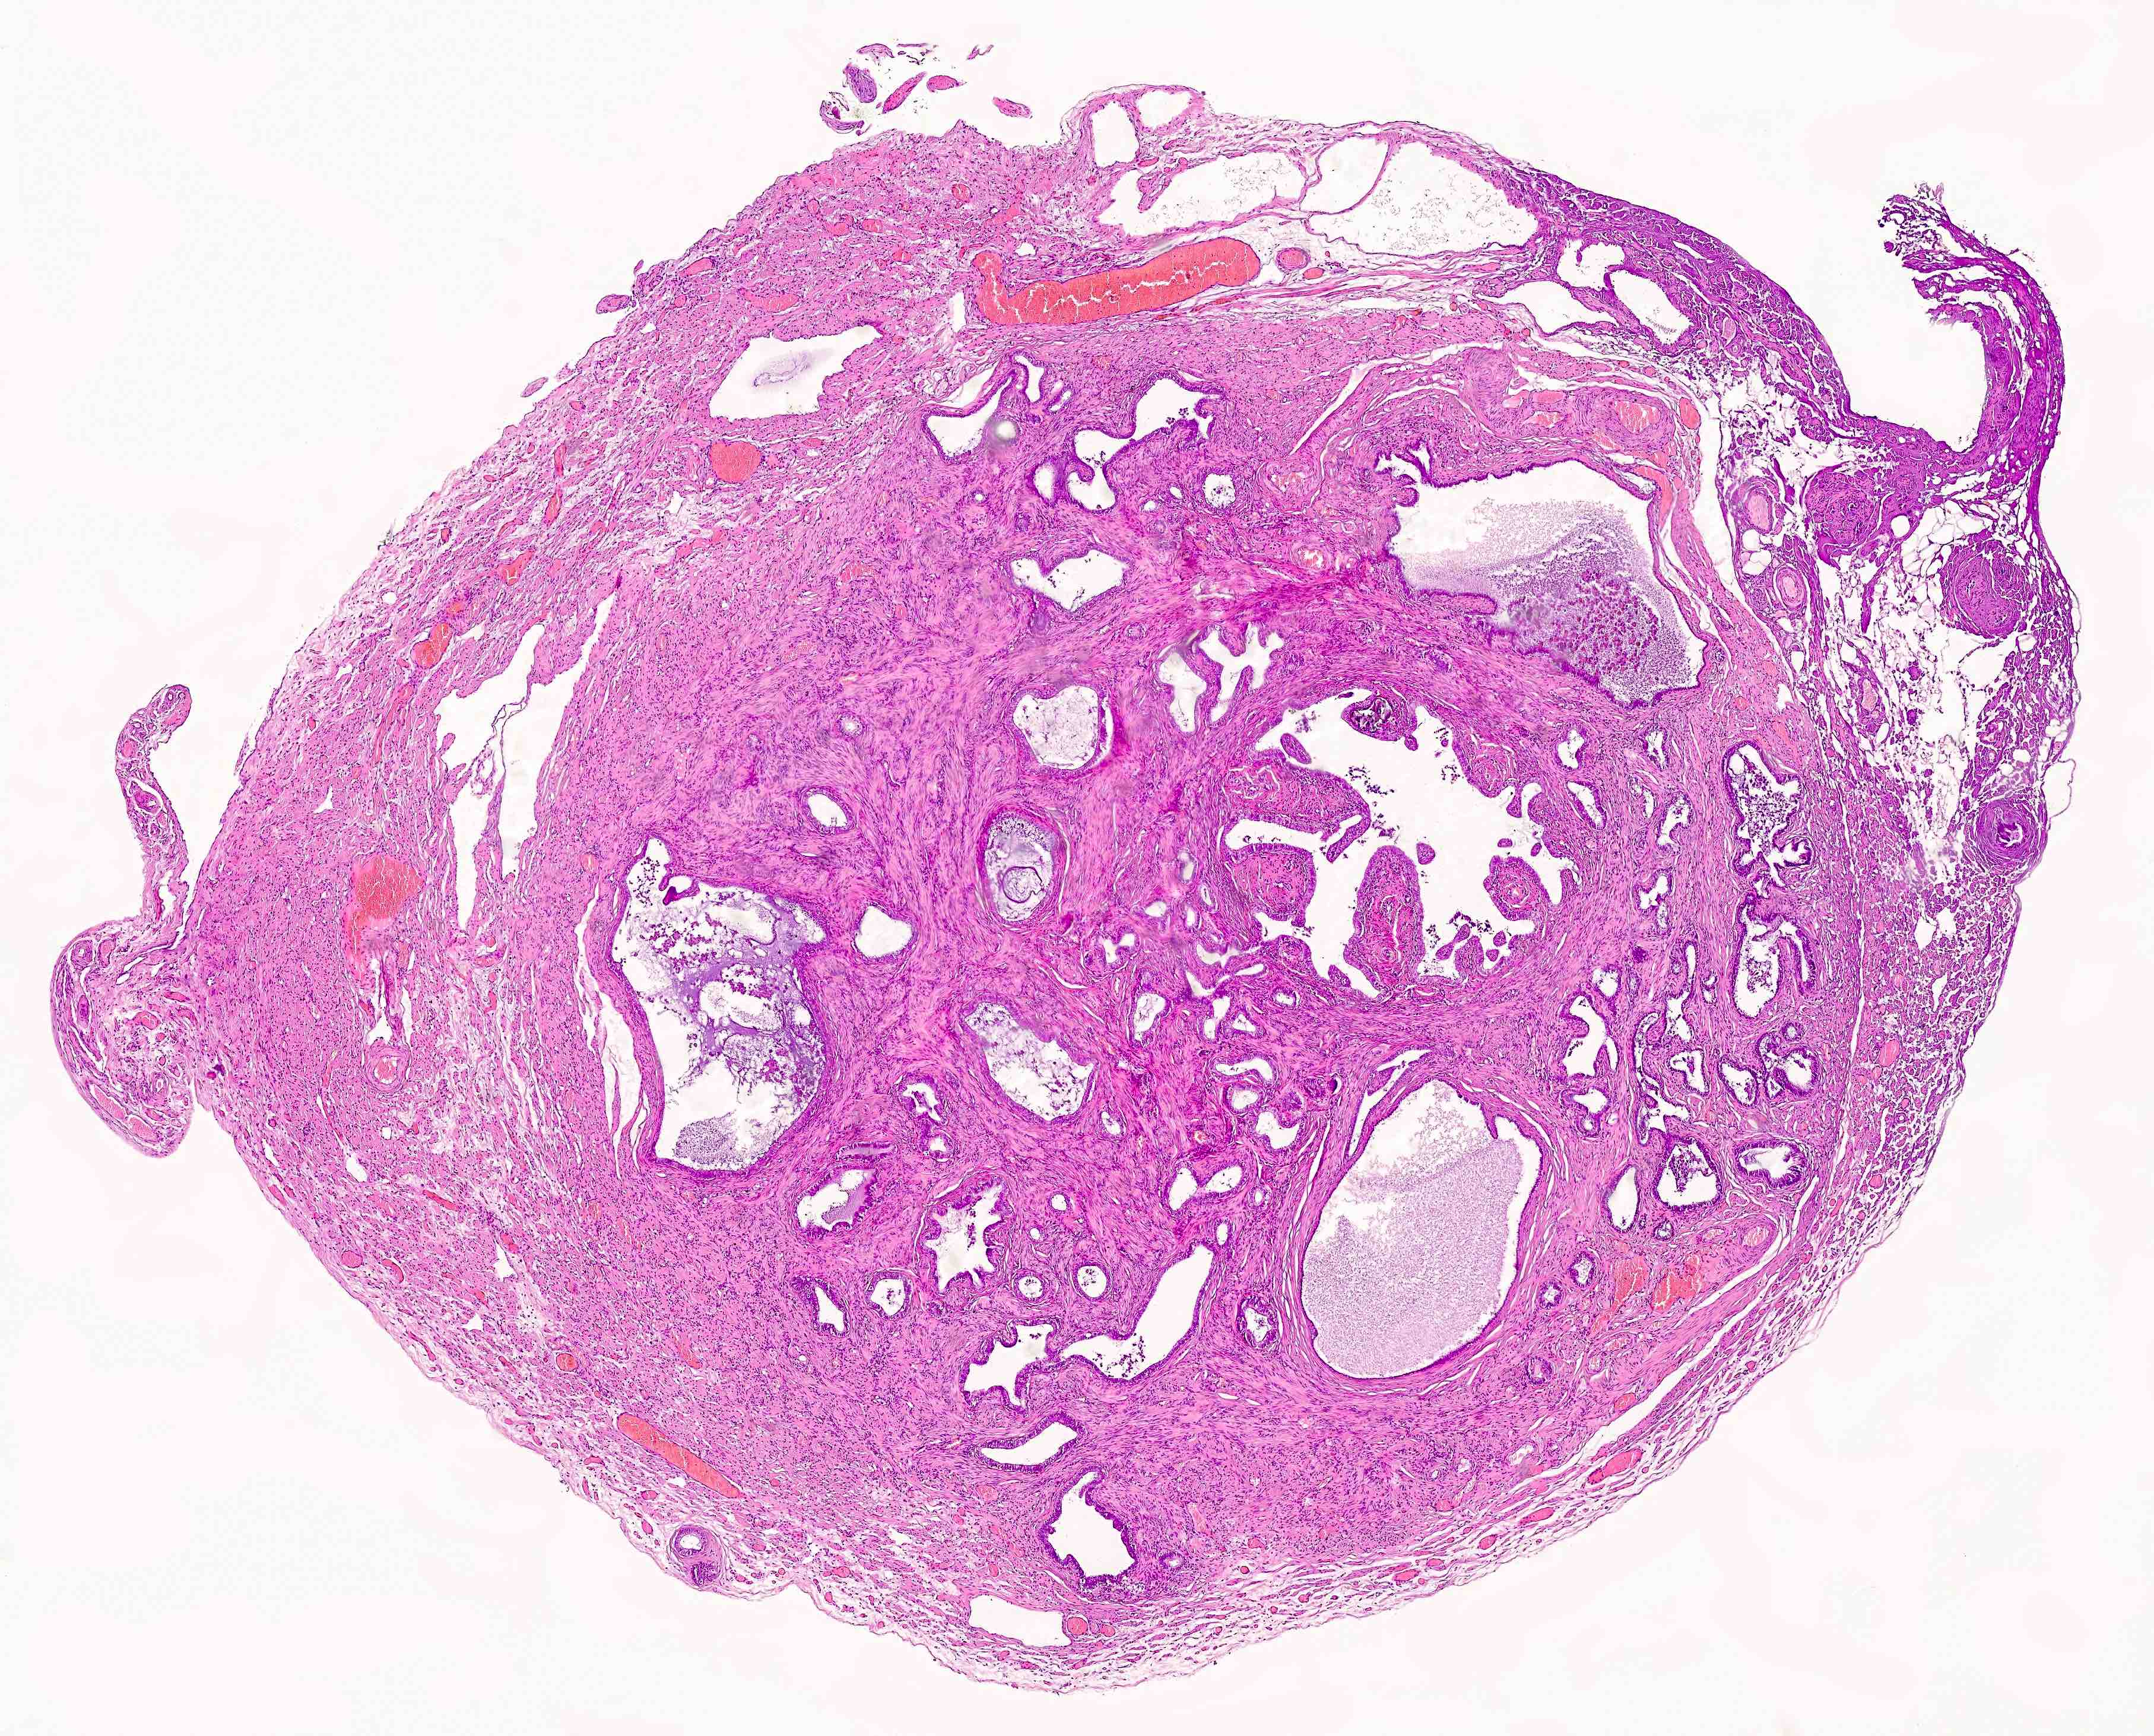

Microscopic (histologic) description

- Regularly spaced glands lined by normal appearing tubal epithelium surrounded by smooth muscle or fibrous tissue

- Tubal lumina are true diverticula that communicate with the central tubal lumen but do not connect with the serosa

- Glands can become cystically dilated (Am J Clin Pathol 1951;21:212)

- No significant atypia, scarring or associated inflammatory / stromal response

- Absence of endometrial stroma differentiates this entity from tubal endometriosis

Microscopic (histologic) images